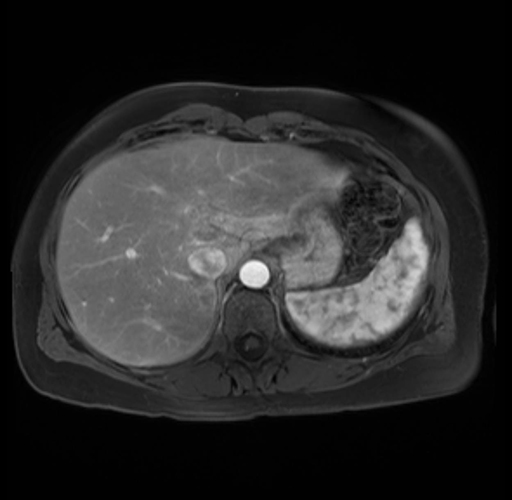

Imaging Analysis

Look through the patient's CT scan to identify any areas of concern for the necessary procedure.

Based on your CT findings, which issue(s) are present and would give reason for "planned slowing down moment(s)" in this case?

Considering a standard distal pancreatectomy procedure, what step(s) of the operation would you do differently in this case?